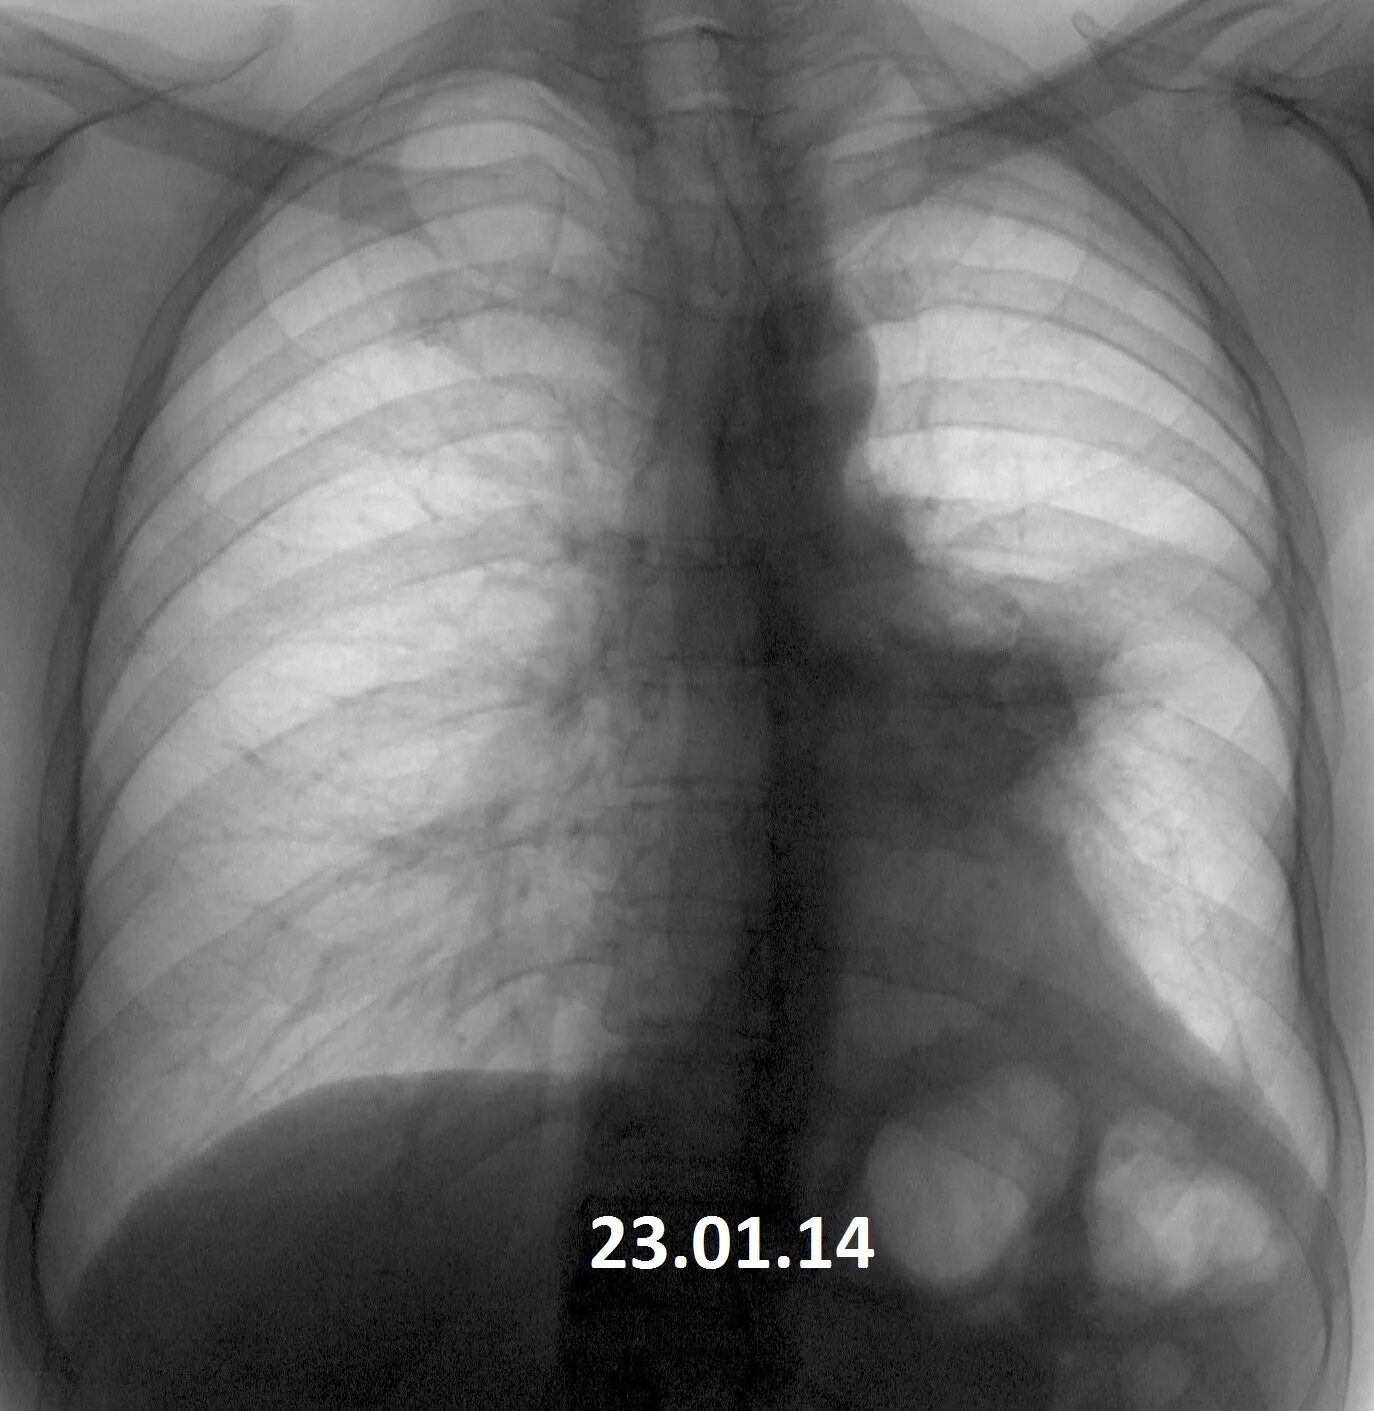

Ошибки кт